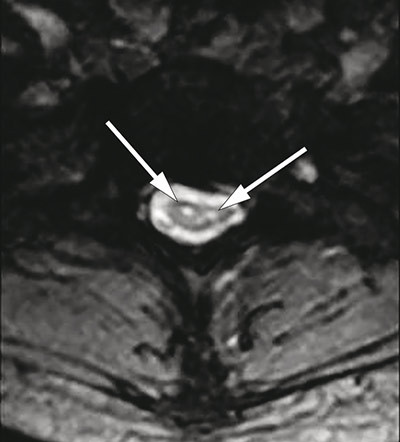

MRI of the spinal cord showed marked atrophy from C4 to Th2 and two longitudinal symmetrical T2-weighted hyperintense lesions from C2 to Th2 (<<<. 3, Fig. 4), confined to the anterior horn area of the medulla. The changes were not considered consistent with syringomyelia, demyelinating plaques, tumour or transverse myelitis. MRI of the head was normal.

Figure 4  Axial T2-weighted MRI of cervical medulla with symmetrical hyperintense lesions localised to the site of the…

Figure 4 Axial T2-weighted MRI of cervical medulla with symmetrical hyperintense lesions localised to the site of the anterior horn cells